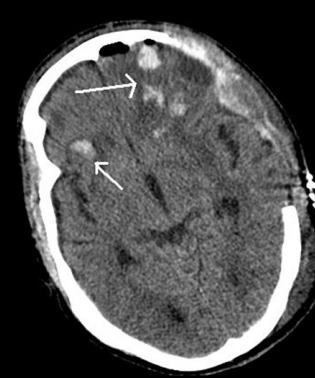

A CT scan of the head revealed a bilateral frontal intraparenchymal hemorrhage, with left frontal, parietal, temporal subdural hematomas (SDH), a left frontal subarachnoid hemorrhage (SAH) with a 7 mm right to left midline shift, cerebral edema and effacement of left frontal horn and right temporal hematoma (Figure 2, his initial CT scan of the head). CT scan of the cervical spine, chest, abdomen, and pelvis were unremarkable.

Figure 2: Shows the following: A CT scan of the head revealed a bilateral frontal intraparenchymal hemorrhage, left frontal, parietal, temporal subdural hematomas (SDH), a left frontal subarachnoid hemorrhage (SAH) with a 7mm right to left midline shift, cerebral edema and effacement of left frontal horn and right temporal hematoma.Case 3: Patient 3 is a 23-year-old female who was an unrestrained passenger involved in a single car MVC (hit a tree) with a fatality at the scene. Patient had a GCS of 3 out of 15 in the field with decerebrate posturing, according to emergency medical personnel. She was immediately intubated by paramedics at the scene.